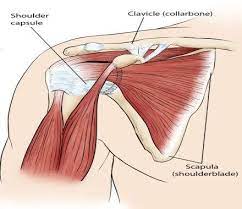

قیمت: 48٬000 تومان - دسته بندی فایل: علوم پزشکیپاورپوینت عضلات کمربند شانه ای

فروش ویژه پاورپوینت حرفه ای عضلات کمربند شانه ای با تخفیف استثنایی فقط 72400 تومان تعداد اسلاید : 34 اسلاید